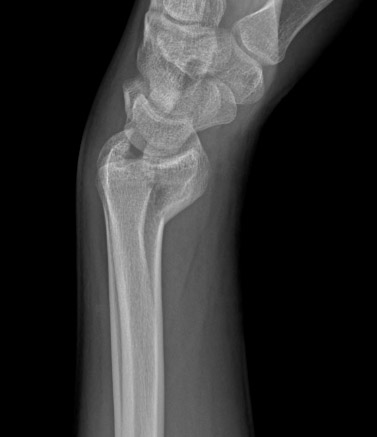

Uma avaliação radiográfica inicial é necessária para se ter um diagnóstico conclusivo de fratura do rádio distal.[30] Geralmente, são feitas radiografias em incidência posteroanterior, lateral e carpal.[30]

As fraturas podem ser fissuras mínimas, fraturas extra-articulares ou fraturas intra-articulares.

A radiografia também pode indicar o grau de osteopenia e dar alguma informação sobre o grau de comprometimento articular ou cominuição.

[Figure caption and citation for the preceding image starts]: Fratura intra-articular do tipo C (complexa) do rádio distal: vista lateralDo acervo do Dr. Chaitanya S. Mudgal [Citation ends].